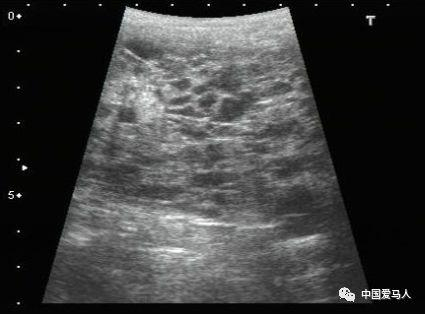

图 可见为子宫中的“沙钱”或“橙片”图像。出现这种图像是因为此时子宫的变化特征。子宫有几个子宫内膜褶皱,增加子宫内膜的表面积。在发情期间,这些褶皱充满了液体,使该区域呈现橙色切片的外观。